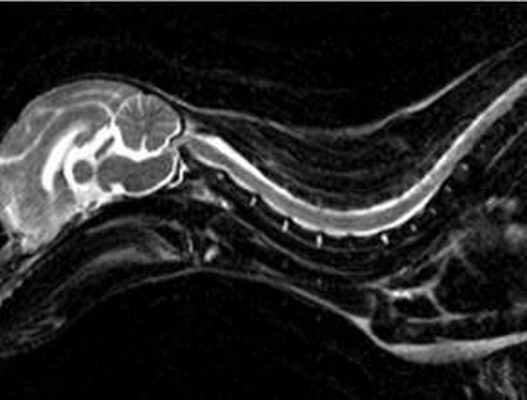

В идеале, лучшим и наиболее информативным методом диагностики атлантоаксиального подвывиха является магниторезонансная томография (МРТ), она более безопасна и дает больше информации о степени сдавления (компрессии) спинного мозга и о наличии сопутствующих заболеваний. Для точной оценки изменений зубовидного отростка второго шейного позвонка, может быть применена компьютерная томография (КТ). Как КТ так и МРТ доступна только в специализированных ветеринарных клиниках.

Данные МРТ позволяют получить более полную информацию об отеке спинного мозга, миеломаляции или сирингогидромиелии (Ягников, 2008).